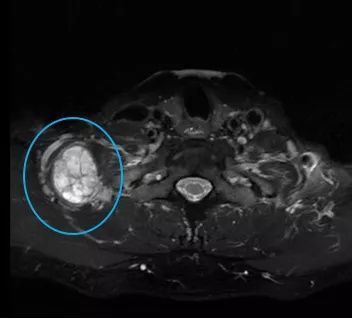

张先生和赵先生住院以后都做了颈部的磁共振检查,检查结果显示张先生的肿块长在了下颌角的边上,肿块还包绕着颈部的大血管。而赵先生的肿块是从臂丛神经上长出来的。

赵先生颈部磁共振 医院供图

张先生的肿块包绕着血管,医生采取了分块切除的方式。而赵先生的肿块则是完整地剥离下来。